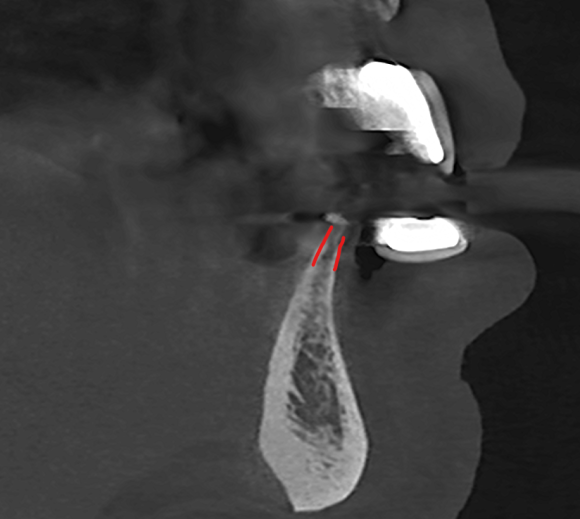

① 심한 치주염으로 골손실이 큰 경우

심한 잇몸 질환으로 치아를 상실했다면, 치아 주변을 감싸고 있던 뼈도 함께 녹아내렸을 가능성이 큽니다.

발치 후 해당 부위가 푹 꺼져 있거나 뼈의 밀도가 낮다면, 임플란트의 탈락을 방지하기 위해 뼈이식이 권장됩니다.

정직한 의료진은 3D CT 데이터 등 객관적인 자료를 바탕으로 환자가 충분히 이해할 수 있도록 설명해 줄 것입니다.